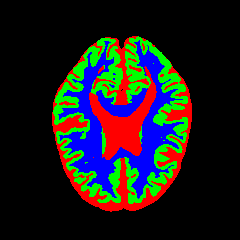

7 Qualitative Evaluation

Fig. 8 and Fig. 10 provide qualitative comparisons on the OASIS-1 and MRBrainS13 datasets, respectively. It is visually evident that the baseline predictions (c) and standard augmentations (e.g., (d), (g), (i)) frequently suffer from noisy artifacts, blurred boundaries, and mis-segmentation of intricate anatomical structures. In stark contrast, our ”Ours+” enhanced methods (e.g., (e), (h), (k)) consistently produce segmentation maps that are visibly cleaner, more spatially coherent, and demonstrate significantly sharper adherence to the Ground Truth (b). This superior fidelity is particularly noticeable in the complex sulcal patterns and holds true across all three backbones (rows), confirming that our framework yields more robust and anatomically plausible results.